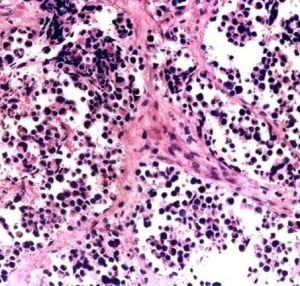

軟組織腫瘤惡性軟組織腫瘤通常生長迅速、體積巨大,浸潤和破壞周圍正常組織。腫瘤本身可有壞死、出血及繼發感染,並且經常有廣泛的血行播散轉移至肺、骨、皮下、腦、腎上腺、胰腺等臟器。患者往往死於惡液質,嚴重出血及廣泛轉移;各種類型的惡性軟組織腫瘤的惡性程度也有顯著差別,根據其血行轉移多少可粗略地分為三類:高度惡性的有圓型細胞脂肪肉瘤、多形性脂肪肉瘤、腺泡狀橫紋肌肉瘤、滑膜肉瘤、血管內皮肉瘤、淋巴管肉瘤等;中度惡性的有深部惡性巨細胞瘤、多形性橫紋肌肉瘤、透明細胞肉瘤、平滑肌肉瘤等;低度惡性的有上皮樣肉瘤、淺部惡性巨細胞瘤、纖維肉瘤、高分化的黏膜脂肪肉瘤等。

軟組織肉瘤共同的特點為:體積比其相應的良性腫瘤大,一般都無包膜。但肉瘤因生長迅速而將周圍正常組織壓縮,可形成假包膜,鏡下觀察與周圍正常組織無明顯界限。

1.腺泡狀排列:

腺泡狀排列可見於腺泡狀軟組織肉瘤和腺泡狀橫紋肌肉瘤;